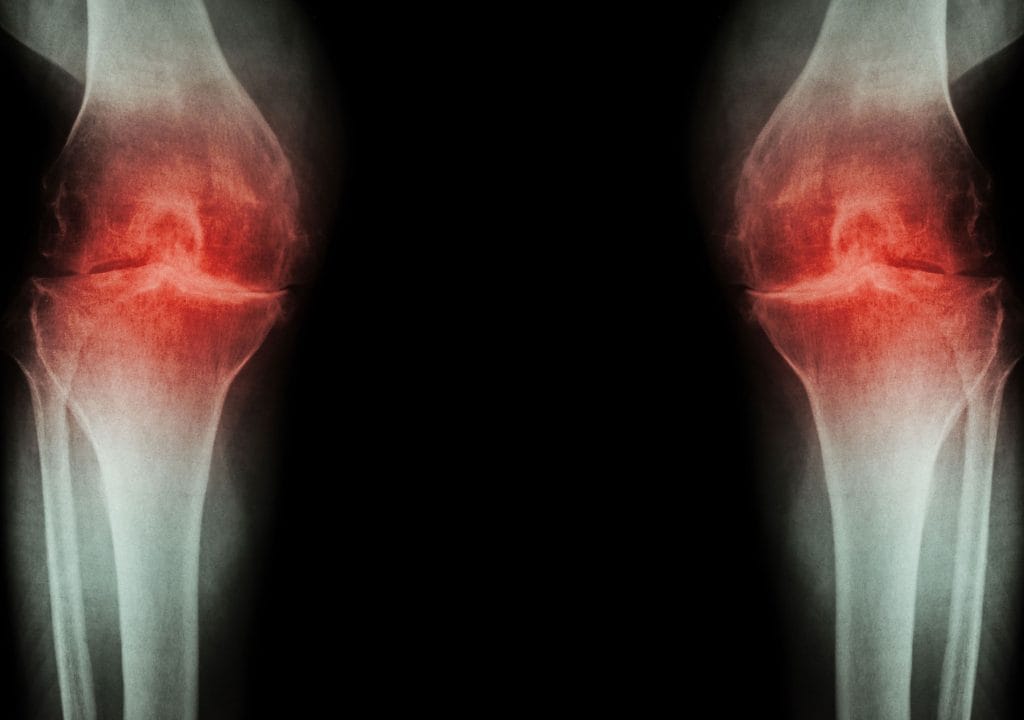

Bolečine v kolenu – vzroki in kaj pomaga

Zakaj pride do bolečine v kolenu, kako prepoznati vzrok in kaj lahko naredite za lajšanje težav.Preberi več

Artroza – simptomi, vzroki in kaj pomaga

Kaj je artroza, zakaj nastane in kako si lahko olajšate težavePreberi več